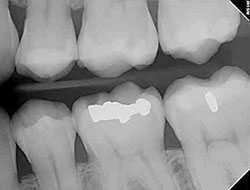

Digital X-rays provide your dentist with high-resolution images of your teeth, which allows them to spot any abnormalities that could be signs of decay. Cavities are one of the most common issues that dentists see in patients. It’s vital to catch these early to treat the issue immediately before it becomes severe and requires more invasive procedures. In most cases, it can be treated with a filling if caught and treated early enough.

The images produced by digital radiography technology are of much higher quality than those created with film. This means it is easier to detect problems with your teeth.